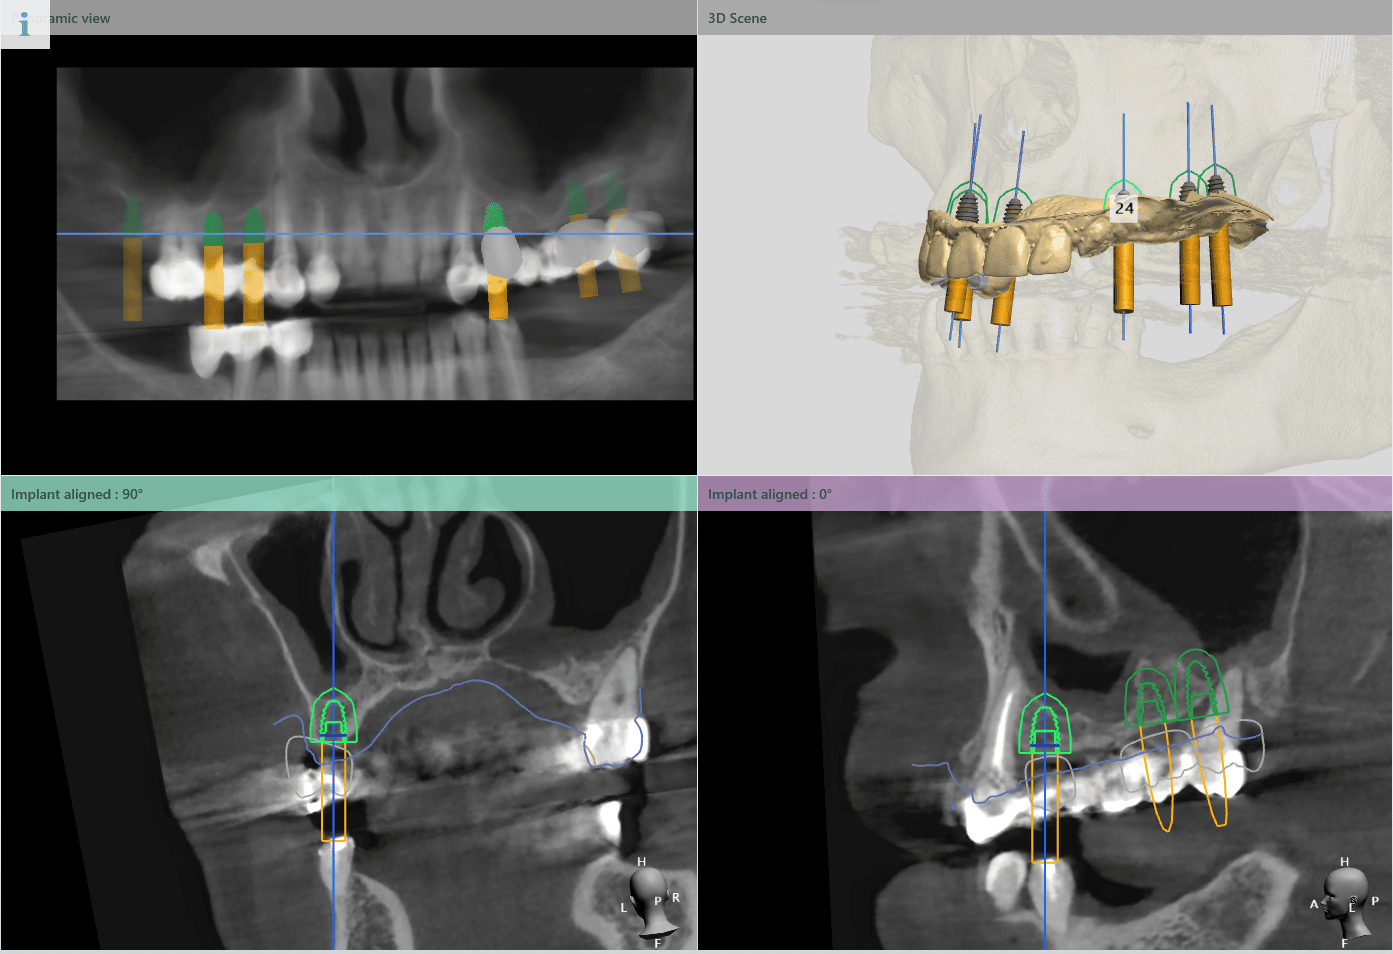

Planul inițial a fost extracția dinților 16 și 28 și inserarea implanturilor în pozițiile 14, 15, 17, 24, 26, 27.

În urma evaluării CBCT-ului s-a constatat necesitatea realizării augmentarii osoase ăn zona posterioară maxilară, lifting sinusal maxilar bilateral odată cu inserarea implanturilor.

Pentru a se asigura că implanturile dentare vor fi plasate în poziția ideală din punct de vedere estetic și funcțional, medical implantolog a recomandat inserarea implanturilor dentare cu ajutorul ghidului chirurgical.

Medicul specialist a efactuat scanarea digitală a arcadelor pe care a trimis-o tehnicianului dentar DigiRay, împreună cu CBCT-ul pacientului.

Odată planficată și agreată poziția și axul de inserție al fiecarui implant, tehnicianul DigiRay efectuează designul șablonului chirurgical și printarea acestuia dintr-o rășină bio-compatibilă.

Medicul a verificat stabilitatea ghidului chirurgical pe dinți. Cu toate că extracțiile dinților 12, 13 și inserarea implantului în pozitia 12 nu au fost planificate în prealabil, ghidul chirurgical a avut stabilitate excelentă.